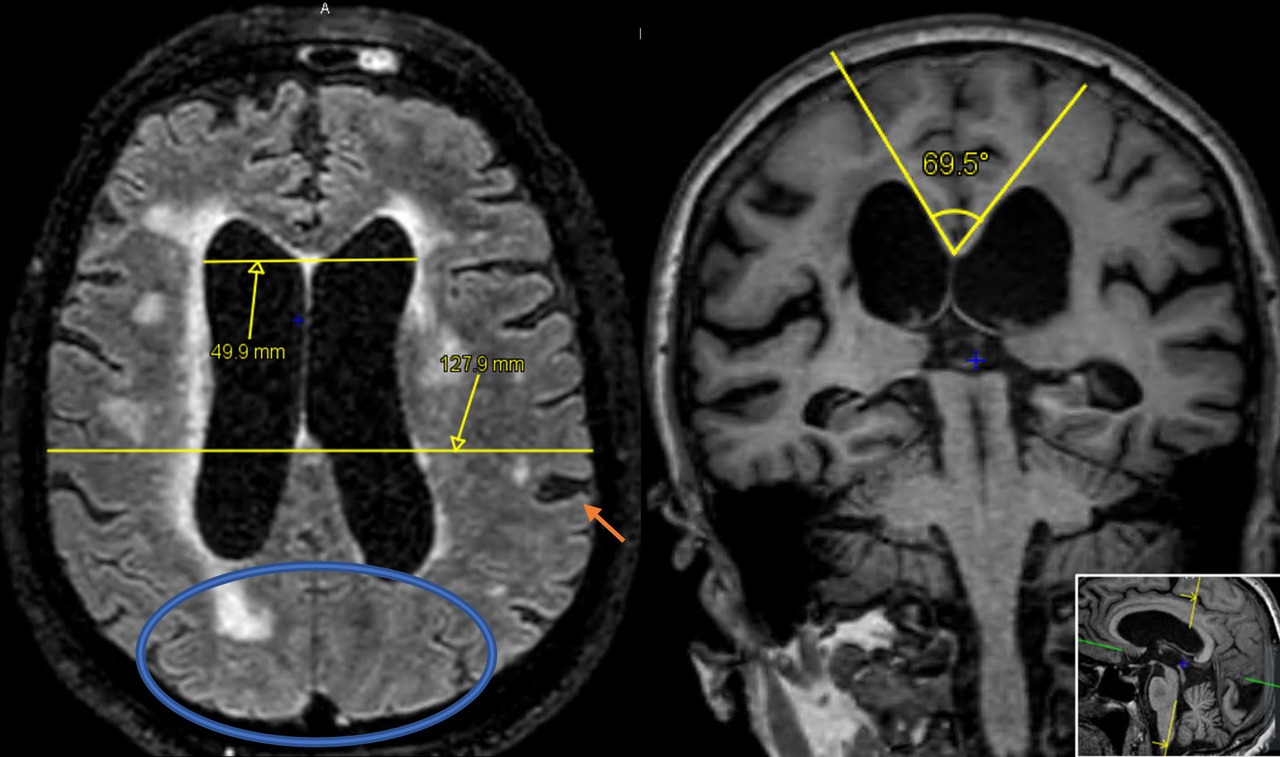

IRM  typique d'une patiente atteinte d'hydrocéphalie à pression normale. L’indice d’Evans est de 0,39. Les sillons postérieurs sont comprimés (ovale bleu), quelques dilatations focales des sillons pariétaux  (flèche orange) sont observées ainsi que des hypersignaux de la substance blanche périventriculaire. L’angle calleux, mesuré sur une ligne perpendiculaire à la ligne CA-CP passant par la CP, est de 69 °.

CA : commissures antérieures ; CP : commissures postérieures.